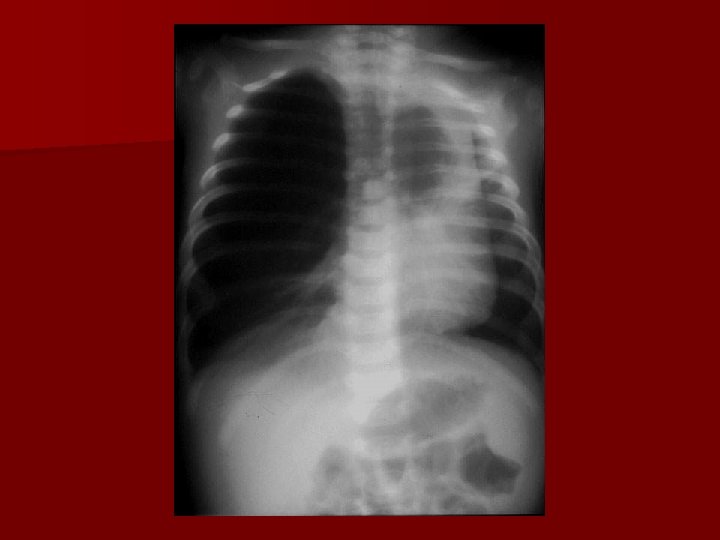

Wady przepony cont. n Wrodzona przepuklina przeponowa Bochdaleka § EMERGENCY !!!!! § 1: 2200 -3500 urodzeń § 85 -90% lewostronna § Współistniejące wady: niedokonany zwrot jelit, sekwestracja płucna, wady serca § Lewostronna: jelito grube, śledzona, żołądek, Prawostronna: wątroba § Hypoplazja płuc (obustronna z przewagą strony zajętej)

Diaphragmatic hernia

1 rok później